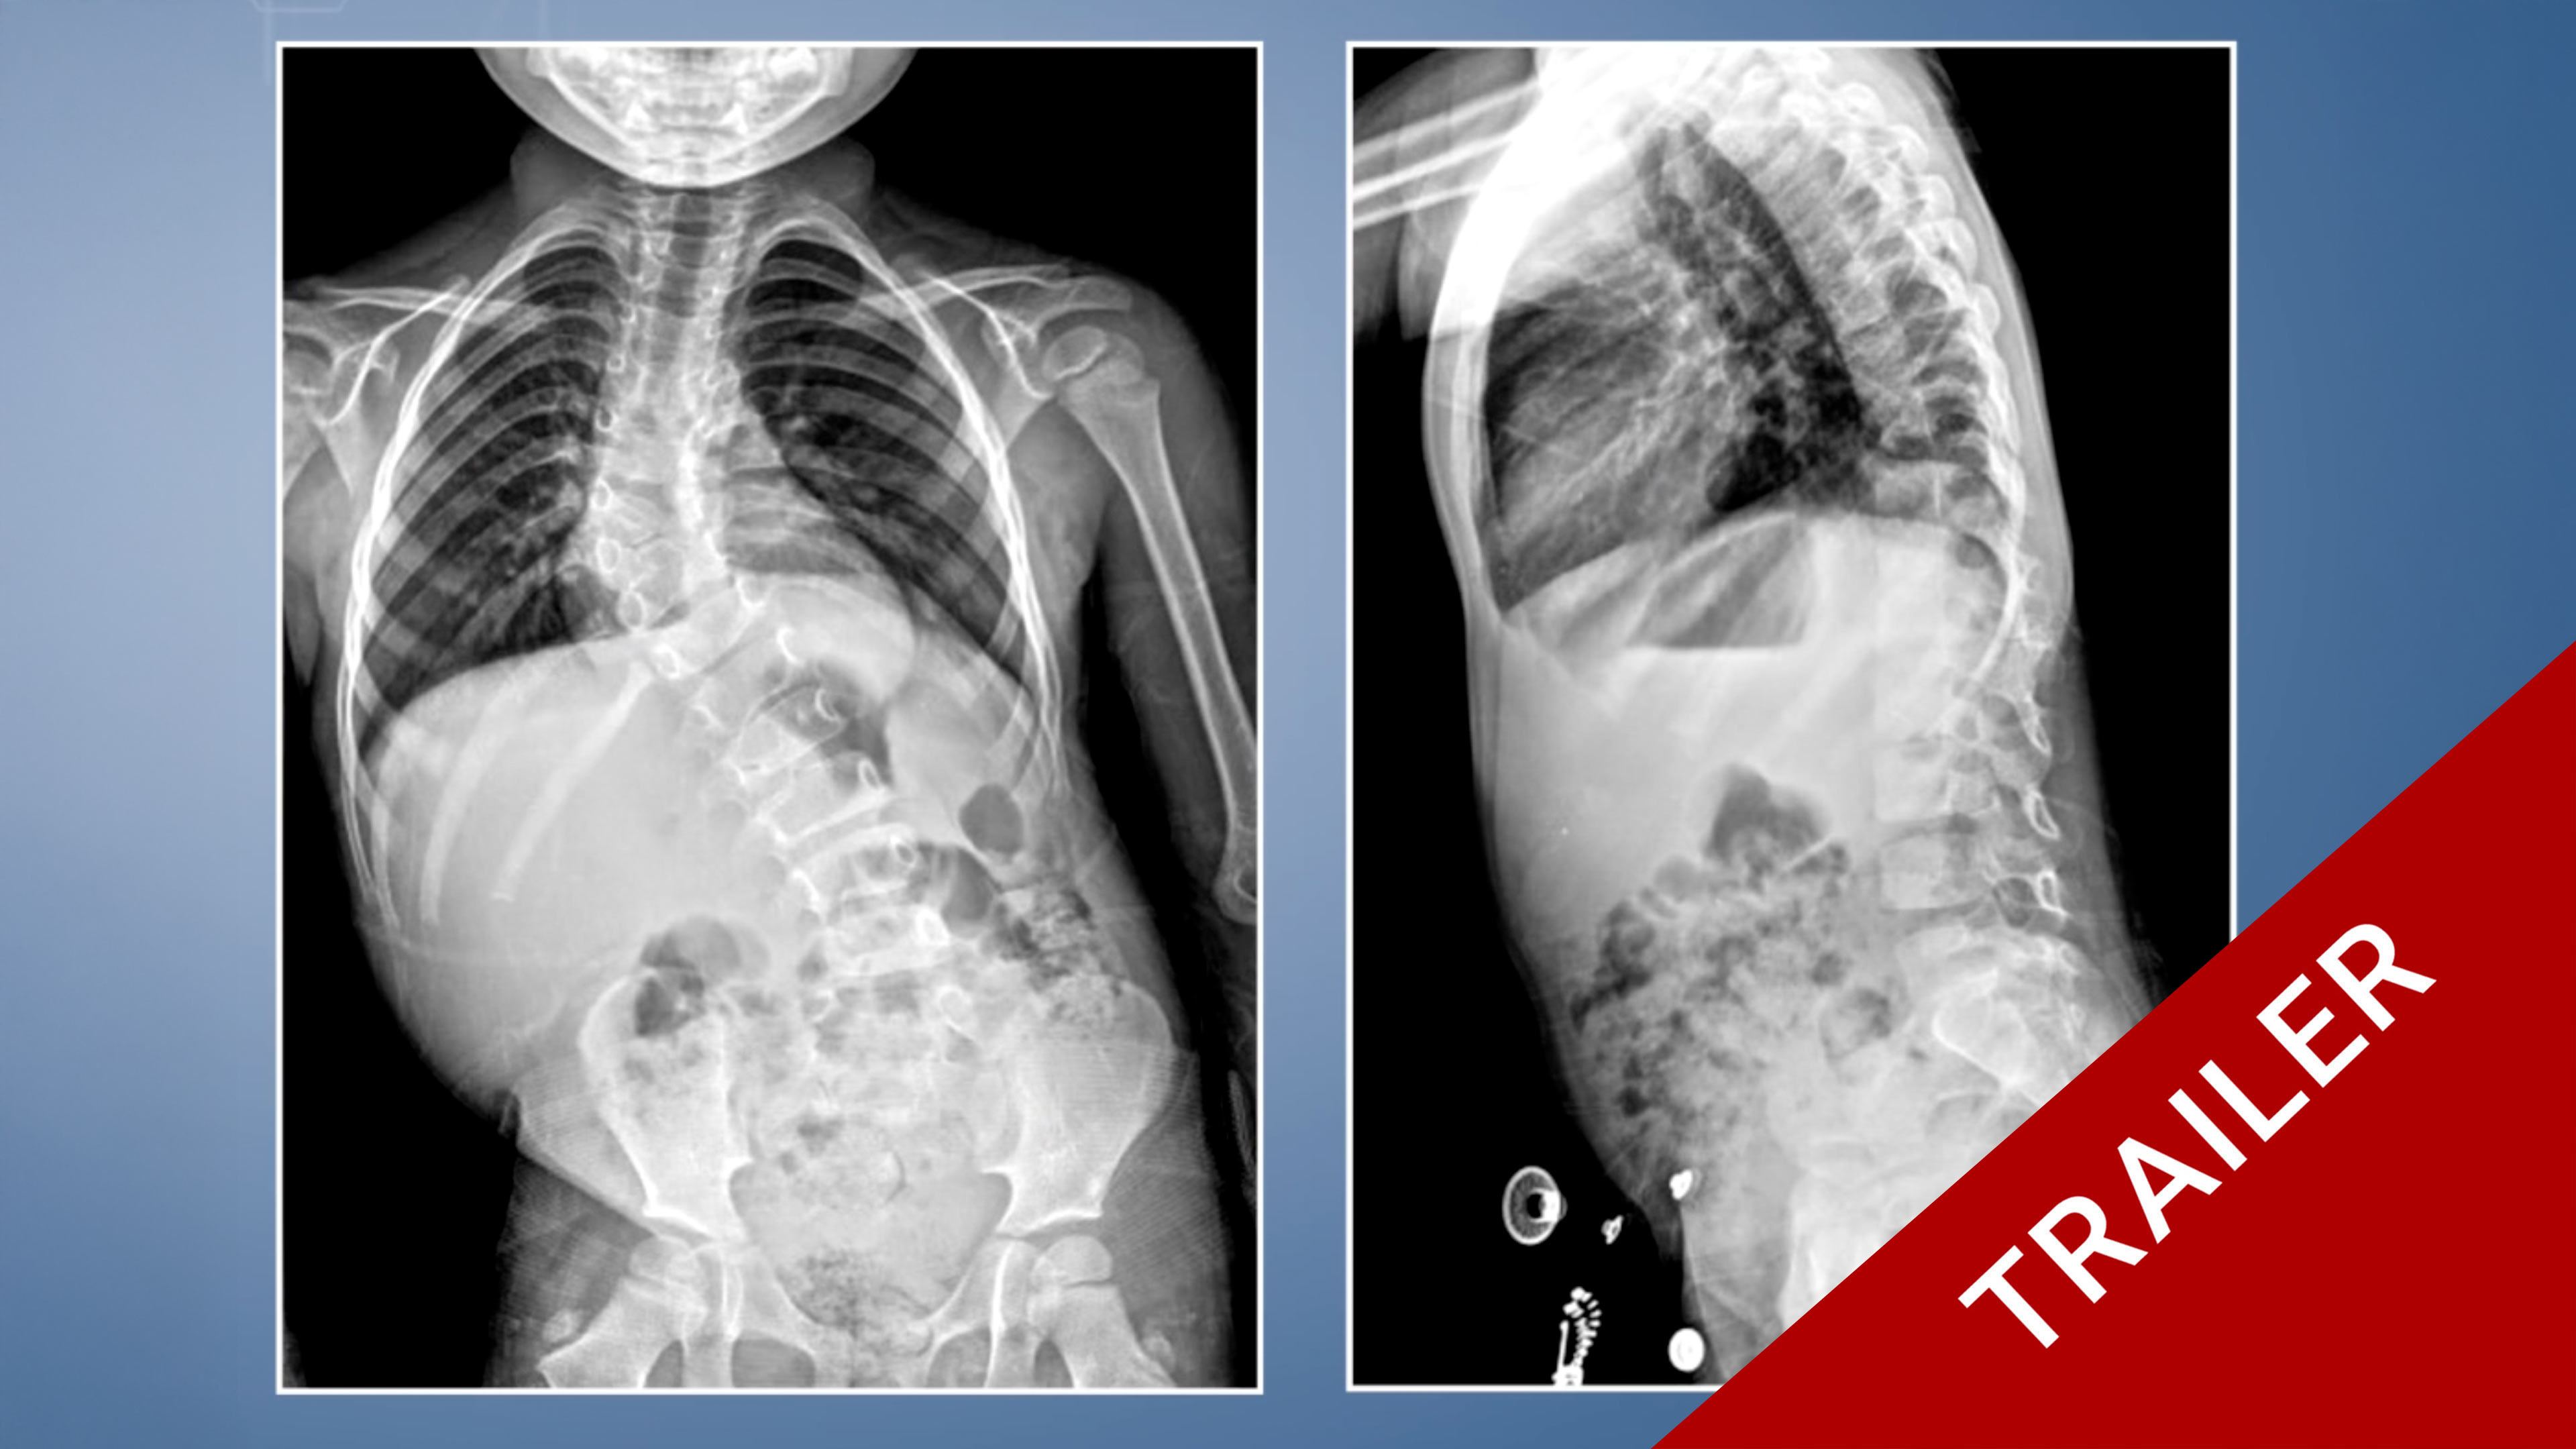

Trailer Resection of Thoracic Hemivertebra in Congenital Scoliosis

Watch the full Video

Antaranyan Ara MD

Aebi Max MD

Wigmore Women's and Children's Hospital

Yerewan

ArmeniaProject 24-019